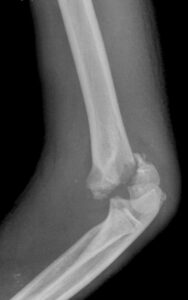

[toggle title=”Anterior Humeral Hat” state=”close”]

Lateral grafide humerus ön yüzeyine paralel ve bitişik çekilen çizgi kapitulumun 1/3 ortasından geçmelidir.

Bu hattın öne ya da arkaya yer değiştirmesi suprakondiler humerus kırığını destekler.

Aynı zamanda suprakondiler kırık hattıyla beraber posterior yağ yastıkçığı bulgusu da görülmekte

Bununla beraber kırık hattı ve posterior yağ yastıkçığı bulgusu da seçilmekte.